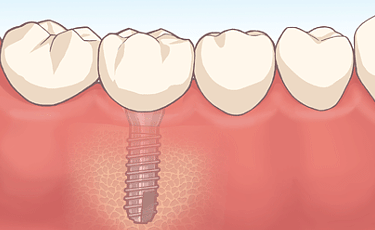

インプラント ![]() |

長年の研究と高度な技術のもとに開発された